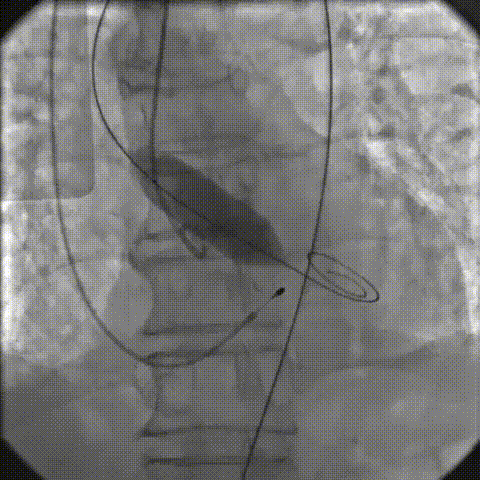

手术影像记录

主动脉根部造影

18mm球囊预扩

AV26瓣膜工作位造影

缓慢脱钩

23mm球囊后扩

后扩后造影:无漏